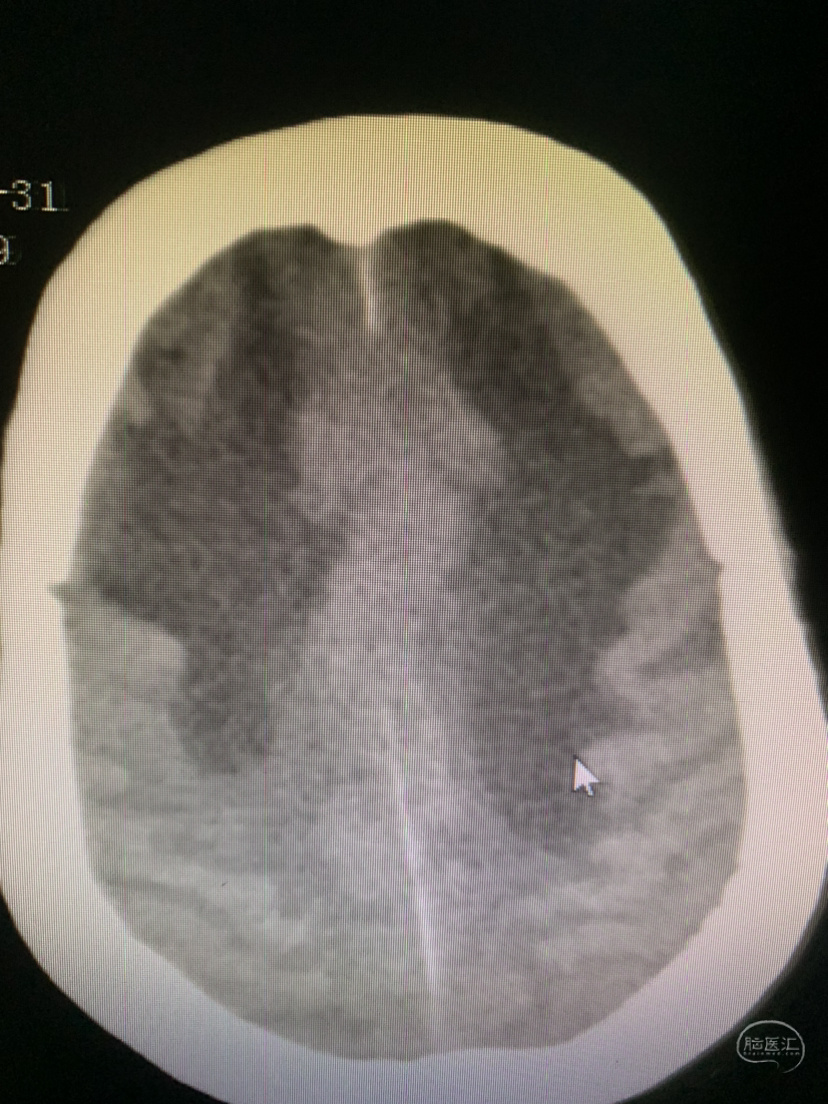

术前CT

术前术后对比

术前CT

术后CT